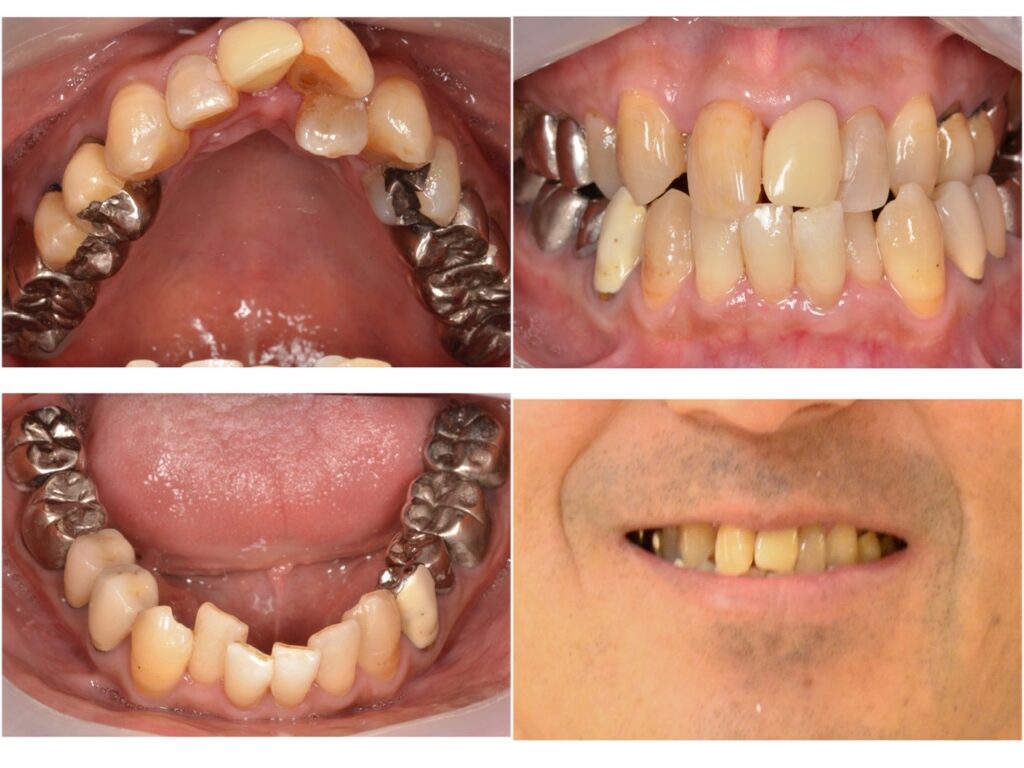

歯並びを改善したい 50代男性 2024.4.9

主訴・術前 歯並びを改善したい 術後の患者様の感想 気になっていた歯並びを改善することができたのでとても満足しています。 銀歯が多く、そこも気になっていましたがセラミックにできたので銀歯の存在も気にすることなく過ごすことができています。 食…